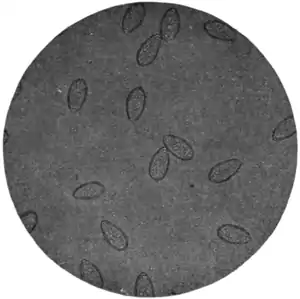

Fig. 165.—Ova of Clonorchis sinensis, x 250.

(Photograph by Dr. John Bell.)

It would be well to bear this parasite in mind in approaching the diagnosis of obscure hepatic disease associated with diarrhœa and jaundice in patients from the East. The discovery of the ova (Fig. 165) in the stools should guide to a correct diagnosis.